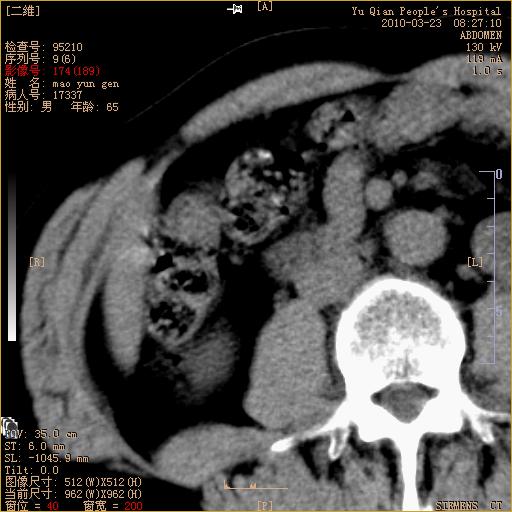

标题: CT25266:消瘦月余,前来肝部检查,请看看肠腔 [打印本页]

标题: CT25266:消瘦月余,前来肝部检查,请看看肠腔

肝区结肠占位,腺癌可考虑,建议肠镜活检。

升结肠肠壁增厚,不均强化,考虑升结肠腺癌可能性,建议肠镜检查。

1)考虑升结肠癌。2)右肾小囊肿。